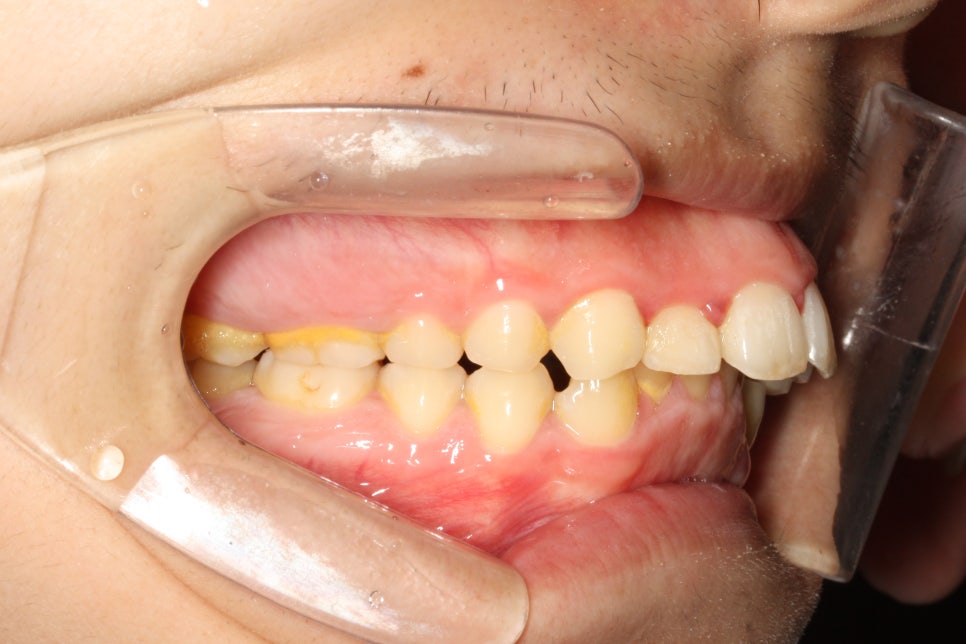

앞니가 많이 돌출되어 있는 환자분이었습니다.

어금니와 송곳니 관계를 보면 발치를 하는 것이 치료를 하는 입장에서 훨씬 편할 수 있는 상태였습니다.

환자분은 심한 무턱과 단안모의 형태를 가진 안모의 소유자였습니다.

이런 분들은 자칫 입이 과하게 들어가면 안모가 많이 안좋아질 수 있죠.

환자분과 상담 후 비발치로 최대한 입을 넣기로 했습니다.